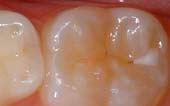

A sealant is a protective coating that is applied to the chewing surfaces (grooves) of the back teeth (premolars and molars), where four out of five cavities in children are found. This sealant acts as a barrier to food, plaque and acid, thus protecting the decay-prone areas of the teeth.

|